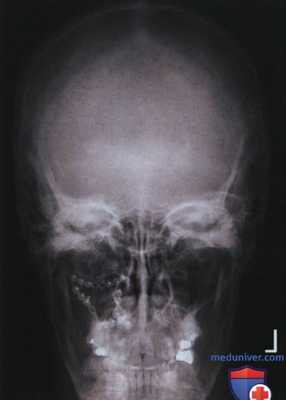

РИСУНОК 1 Рентгенограммы черепа в ЗП и ПЗ проекциях, правильное расположение. РИСУНОК 2 Рентгенограмма нижней челюсти в ЗП проекции, правильное расположение.

• Нижняя челюсть: расстояние между ветвью нижней челюсти и латеральным краем шейных позвонков с обеих сторон одинаково, ветви нижней челюсти имеют одинаковую ширину (рис. 5)

РИСУНОК 3 Правильное положение пациента для рентгенографии черепа в ЗП проекции. РИСУНОК 4 Рентгенограмма черепа в ЗП проекции. Голова была повернута лицом влево. РИСУНОК 5 Рентгенограмма нижней челюсти в ЗП проекции. Голова была повернута лицом вправо. РИСУНОК 6 Рентгенограмма черепа в ЗП проекции. Подбородок был опущен недостаточно, чтобы расположить ОМЛ перпендикулярно ПИ. РИСУНОК 7 Рентгенограмма черепа в ЗП проекции. Подбородок был опущен избыточно, чтобы расположить ОМЛ перпендикулярно ПИ.

б) Нижняя челюсть: ротация. Если на рентгенограмме нижней челюсти в ЗП проекции расстояние между ветвью нижней челюсти и латеральным краем шейных позвонков с одной стороны больше, чем с другой, то голова была повернута лицом в ту сторону, на которой указанное расстояние меньше. Также с этой стороны ветвь нижней челюсти будет уже (рис. 5).

Рентгенограмма 2:

ЗП проекция черепа.

а) Анализ. Каменистые гребни визуализируются ниже надглазничных краев; спинка турецкого седла и передние наклоненные отростки тела клиновидной кости накладываются на пазухи решетчатой кости. Подбородок был опущен недостаточно, чтобы расположить ОМЛ перпендикулярно ПИ.

б) Коррекция. Опустите подбородок так, чтобы ОМЛ была перпендикулярна ПИ, или опустите его на расстояние, равное промежутку между каменистыми гребнями и надглазничными краями.